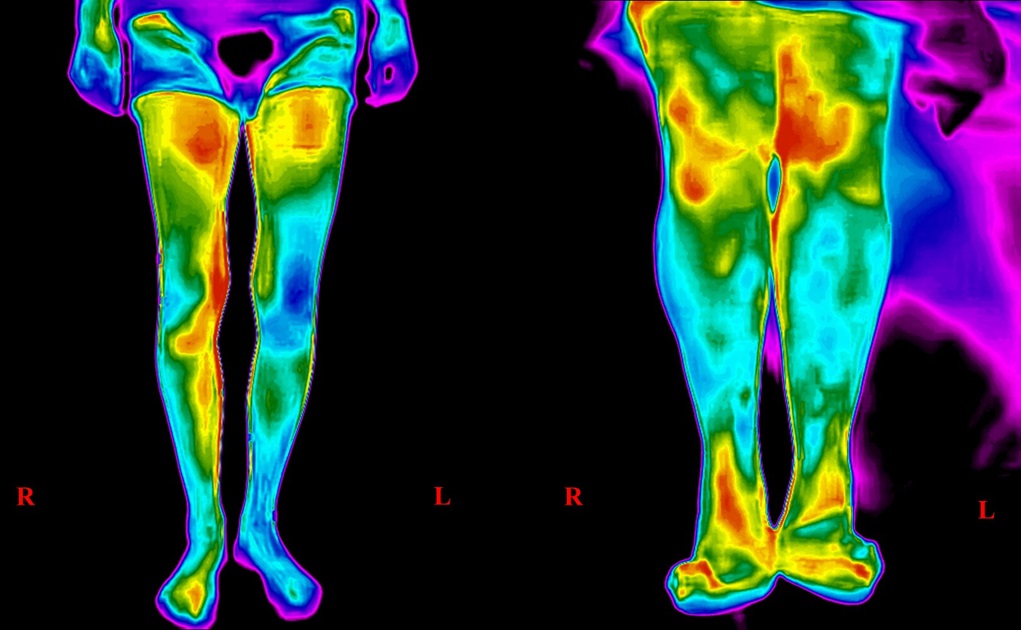

Изследването е дигитално обработена инфрачервена термография, базирана на изкуствен интелект, чрез която могат много рано да се разпознаят проблеми на мозъчните и на периферните съдове.

Инфрачервената термография е ефективна както за откриване на сърдечносъдови, така и на онкологични заболявания. Първи опити за термовизуална дигностика са правени още в средата на ХХ век. Но напоследък се развиват базираните на изкуствен интелект софтуерни технологии, даващи възможност за получаване на образ с много висока резолюция, която позволява на лекарите с изключителна прецизност да разграничат патологичната съдова зона от околните тъкани. Така може да се установи точно къде има съдов проблем.

Когато лекарят установи промяна на температурата на една зона на човешкото тяло в сравнение с околните тъкани, независимо дали е повишение или намаляване на температурата - е на лице съмнение за заболяване на този орган. Когато се регистрира понижаване на температурата на горен или долен крайник или ако невролог в симптоматиката, която един пациент му споменава, има съмнение за стеснение на съд, кръвоснабдяващ крайника, може да се приложи този метод. Изключително безвреден е, тъй като не се използват рентгенови лъчи, нито контрастна материя, която не е безобидна за бъбреците. Нито се разчита на субективното усещане на ръката на специалиста, който се опитва да установи дали температурата е ниска или висока. Температурата се измерва с термокамера, базирана на добра резолюция. И тези образи в резултата на обработката с изкуствен интелект предоставят информация за зоната колко добре е кръвоснабдена. Дори и в такива зони като черепа може да се установи дали една съдова територия е различна спрямо друга съдова територия въз основа на температурата. Недобре кръвоснабдените участъци са оцветени в определен цвят и много отчетливо може да се види къде има страдание или напълно запушени съдове. След възстановяване на кръвотока в запушения съд, мястото вече е оцветено в жълто ли червено.